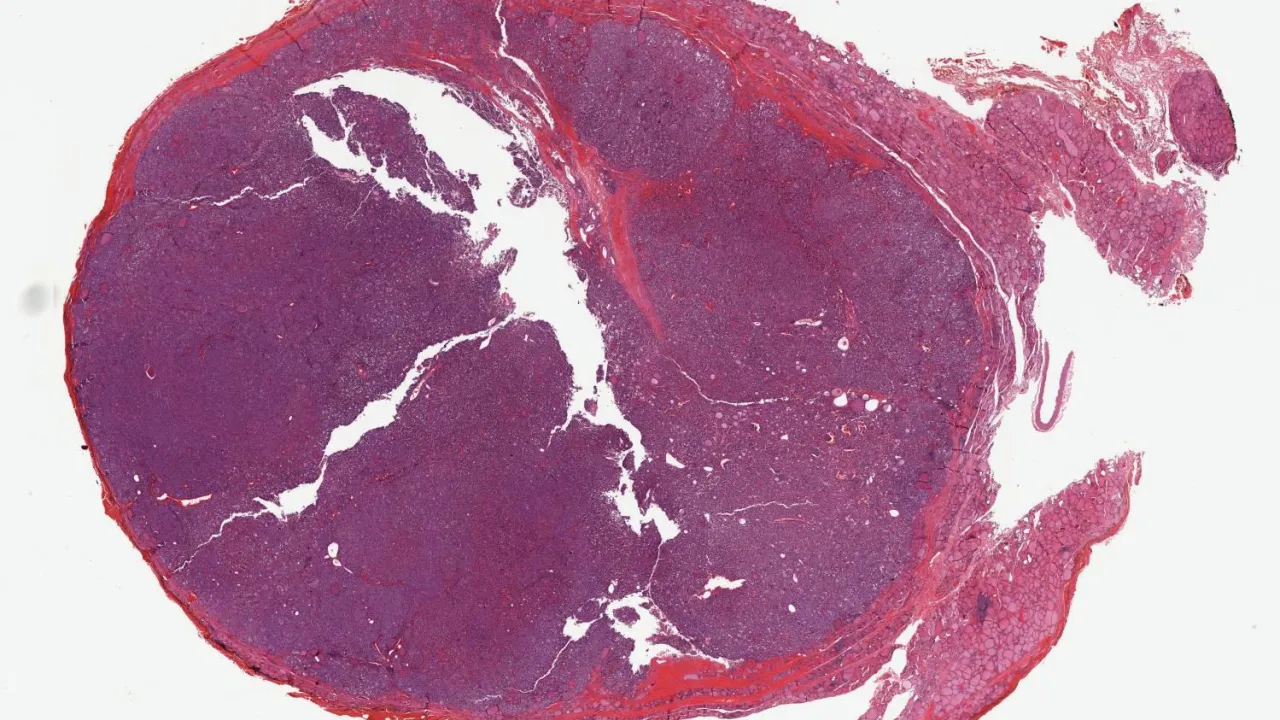

Lymph node, Metastatic papillary thyroid carcinoma

Lymph nodes, Small lymphocytic lymphoma/Chronic lymphocytic leukemia, H&E stain